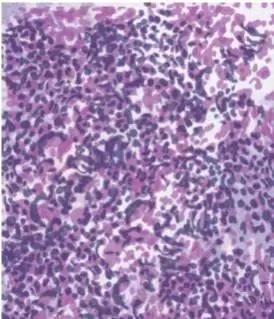

非小细胞型肺癌,包括鳞癌、腺癌、大细胞癌,与小细胞癌相比其癌细胞生长分裂较慢,扩散转移相对较晚。非小细胞肺癌约占肺癌总敉的80-85%。

小细胞肺癌是肺癌的基本类型之一,属于未分化癌,其病理类型包括燕麦细胞型、中间细胞型和复合燕麦细胞型。三分之一的肺癌患者属于这种类型。小细胞肺癌是一种恶性程度较高的肿瘤,生物学行为恶劣,预后凶险。以同样播散范围比较,小细胞肺癌较其他类型肺癌诊断前的症状期短,确诊后的生存期亦短。如不治疗,小细胞肺癌患者自诊断起的中位生存期不足三个月,二年生存率小于1%。发病年龄较轻,多见于男性,多数病人有吸烟史。一般起源于较大支气管,大多为中央型肺癌。小细胞癌分化程度低,生长快,较早出现淋巴道转移和侵入血管经血道广泛转移到身体远处器官组织,因此在各类肺癌中,小细胞癌的预后最差。小细胞癌对放射治疗或抗癌药物治疗敏感度高。 治疗上一般不主张手术,以全身化疗及放疗为主,该类型肺癌恶性程度较高,预后较差。患者有发热、咳嗽都是肺癌常见的症状,出现头痛要警惕脑转移,强烈建议行颅脑CT检查。

非小细胞型肺癌,包括鳞癌、腺癌、大细胞癌,与小细胞癌相比其癌细胞生长分裂较慢,扩散转移相对较晚。非小细胞肺癌约占肺癌总敉的80-85%。 非小细胞肺癌的治疗要根据肺癌的临床分期来进行。对Ⅰ、Ⅱ、ⅢA期主要以手术切除为主,淋巴转移显著者,于手术前可辅以化疗或放疗。非小细胞肺癌是是肺癌组织病理分类中的一类,包括鳞癌、腺癌、大细胞癌,其他(腺鳞癌、类癌、肉瘤样癌、唾液腺型癌等)